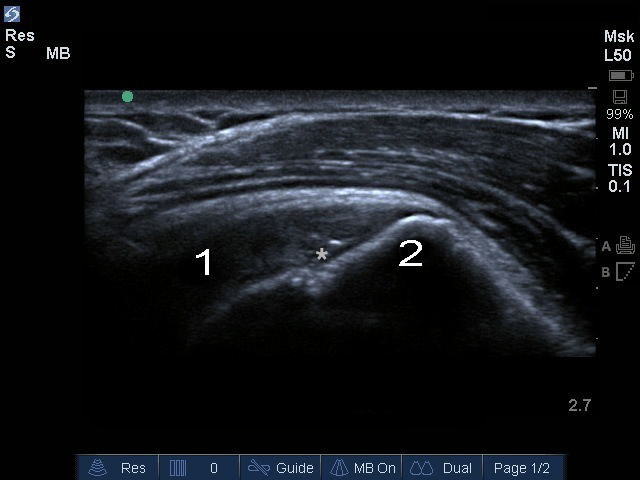

肩部冈上肌骨皮质不规则图像

星号:冈上肌关节面撕裂

冈上肌

大结节 (GT)